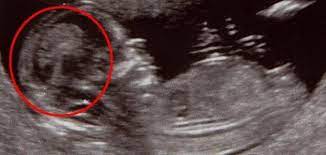

متى يبان نوع الجنين البنت

متى يبان نوع الجنين البنت.

متى يبان نوع الجنين الولد